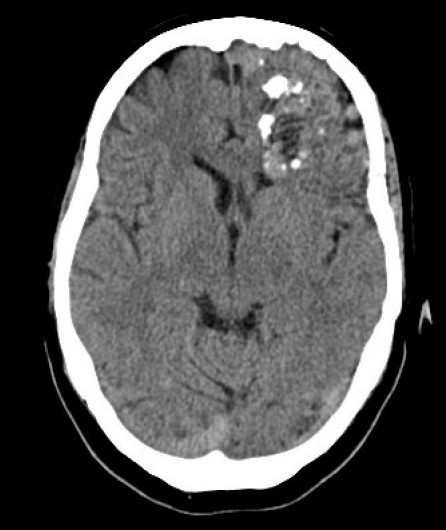

Lésions vasculaires (MAV-fistules-Moya-Moya) cérébrales et médullaires

Nerveux Vasculaire DES SPECIALITE Cerveau